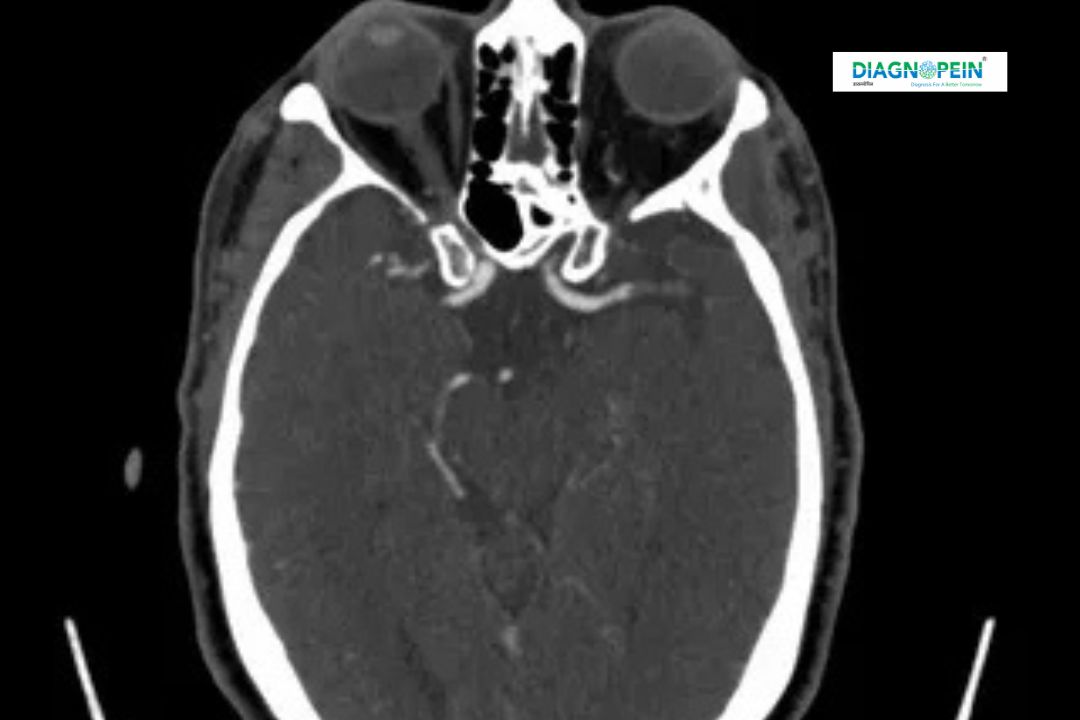

X-RAY RIGHT MASTOID SCHULLER’S VIEW is a specialized radiographic imaging technique used to evaluate the mastoid air cells and surrounding temporal bone structures of the right ear. This view provides a clear lateral projection of the mastoid region, helping doctors assess infections, inflammation, trauma, or structural abnormalities. It is commonly recommended by ENT specialists for patients experiencing chronic ear pain, discharge, hearing loss, or suspected mastoiditis.

X-RAY RIGHT MASTOID SCHULLER’S VIEW plays a crucial role in detecting diseases of the mastoid bone, which is connected to the middle ear. The mastoid contains air-filled spaces that can become infected if middle ear infections are left untreated. This X-ray view helps identify opacification, sclerosis, erosion, or fluid levels in mastoid air cells.